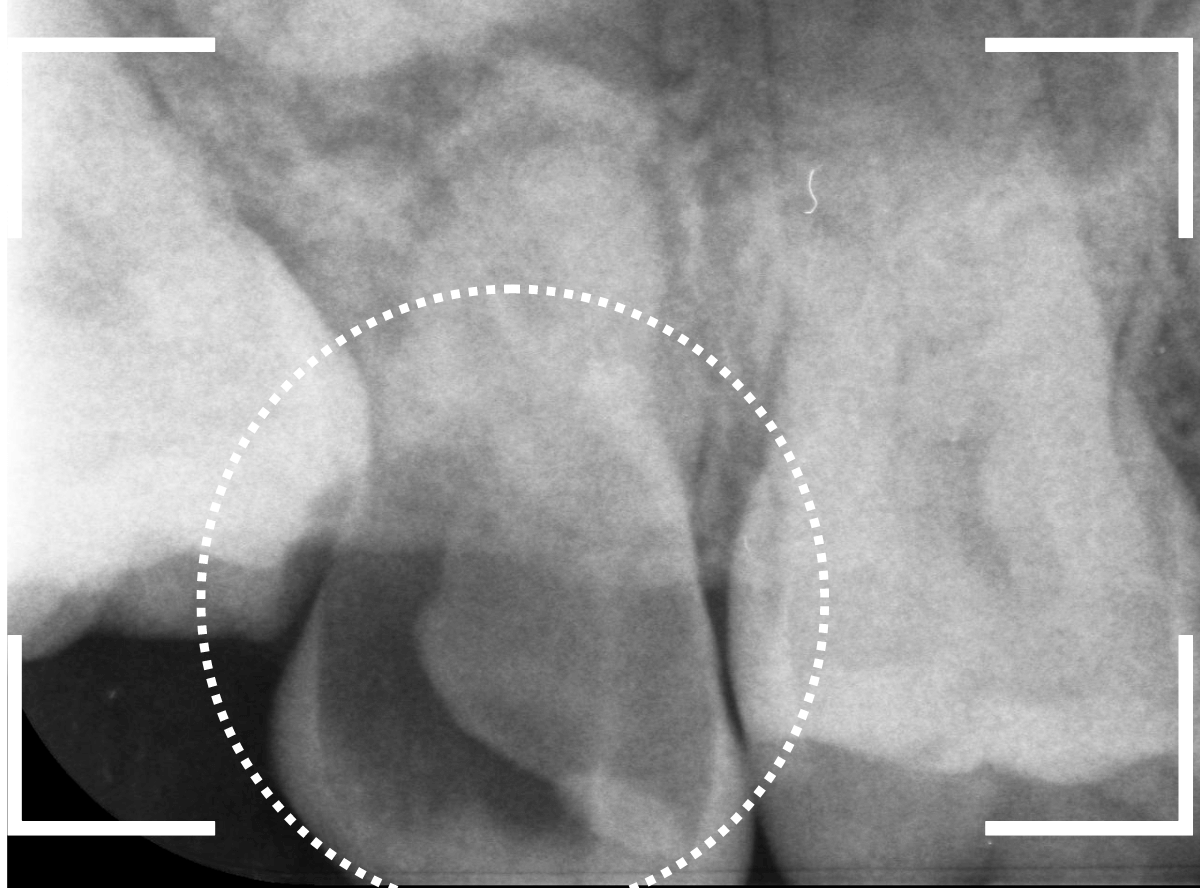

レントゲン写真で確認します。

一つ手前の歯も大きな虫歯で根元までボロボロです。

これではどちらが痛みの原因になってもおかしくありません。

側面から確認します。

手前の歯の根元がボロボロなのも確認できます。